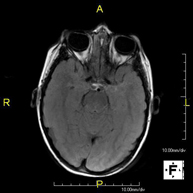

- RM Cerebral (craneal)

Prueba diagnóstica no invasiva que consiste en la obtención de imágenes de alta definición anatómica del cerebro mediante el empleo de un campo electromagnético y ondas de radio (con un emisor y un receptor). No utiliza radiación ionizante. Indicaciones: problemas vasculares, pérdida de memoria, epilepsia, cefalea, malformaciones, sospecha de tumor, meningitis. - RM Cais